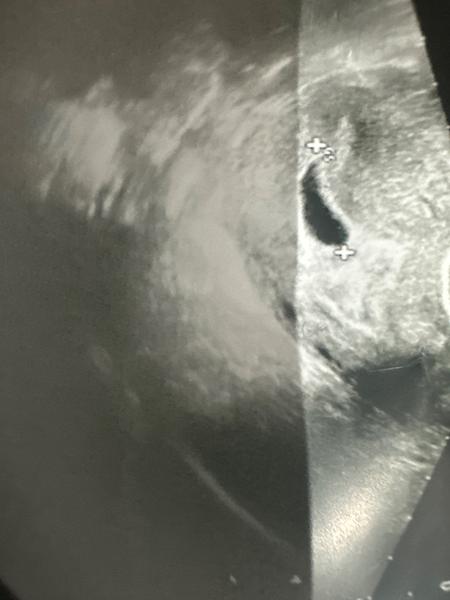

Prázdny vak v 7. týždni tehotenstva: Aké sú vaše skúsenosti?

@bambieblue myslíš že je to koniec? Povedali mi len že treba čakať ako sa to vyvinie, vraj môže byť skoro tak neviem

@dagas tak držím palce že to dobre dopadlo 🙏 vôbec neviem čo si myslieť ale mám strach že to dopadne zle 🥺 o 2 dni idem opäť tak snáď budem o niečo múdrejšia, zatiaľ verím v zázrak

3x som mala v približne rovnakom tt prázdne gestacne vaky. Tiež som mala prísť o 2-3 týždne na kontrolu. 2 tieto prázdne gestacne vaky mi momentálne spia v detskej izbe ale bohužiaľ ten 1 bol zamlknuty potrat. Takže naozaj to ešte môže dopadnúť hocijako. Je to 50:50. Držím silno palce 🙏